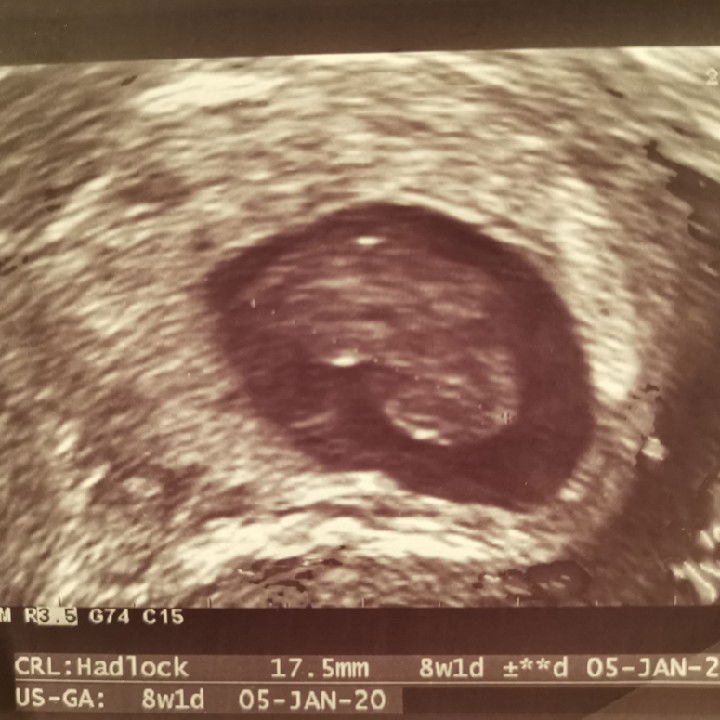

I thought I would pen down my feelings here... Everything was going so smoothly for my wife until our second appt with the obgyn dr at 9 weeks pregnancy. We waited for our turn and normally we would do the transvaginal ultrasound for each visit. The nurse prepped my wife and waited for the Dr to start the procedure. After scanning for a while, her facial expression changed. Something was amiss. Normally, you would be seeing something flickering at the centre of the foetus. That would be the foetal heartbeat. It was quiet. Empty. Measuring the foetus, it is only 17.44mm and estimated 8 weeks old. The Dr pressed some dials and changed to Doppler setting showing red/blue colour indicating active blood flow. The Dr suggested that we do another scan for second opinion at the hospital the next day. We went back home and prayed to the Lord for a miracle. Second day came and we proceeded to the hospital for the second scan. We waited for about 1½h as we had no appt. This time, the sonographer did a transabdonimal ultrasound before a transvaginal ultrasound. Seeing the same picture on the monitor devastates me again. This time, the Prof came and take a look to confirm the missing foetal heartbeat. The thought of the baby gone is really heart-wrenching. No parents would want this to happen.